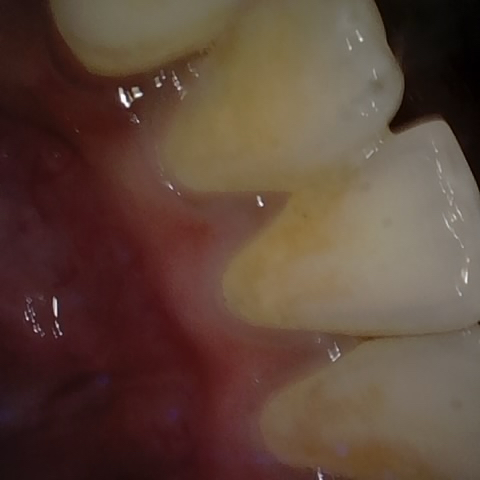

Annotated as "Good"